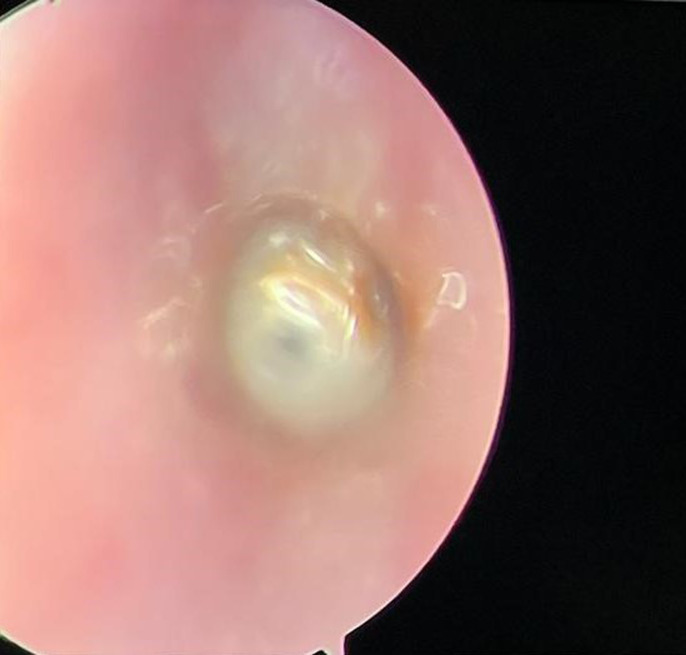

吸入异物在儿童中很常见,可能会危及生命。可以发现不同类型的异物,但喉部定位是罕见的。我们在此报告一例8个月大的男婴谁提出呼吸窘迫,发音困难,和喘。入院时,患儿表现出严重的喉部呼吸困难。颈椎CT扫描显示喉部有一不透射线的异物。内窥镜提取显示声门下有一阻生鱼椎体。位于下气道喉部的异物是罕见的,发现鱼椎骨是例外。

Inhalation of foreign bodies, a common occurrence in children, can be life-threatening. Different types of foreign bodies can be found, but laryngeal localization is rare. We here report the case of an 8-month-old male infant who presented with respiratory distress, dysphonia, and stridor. On admission, the child exhibited severe laryngeal dyspnea. Cervical CT scan revealed a radiopaque foreign body in the larynx. Endoscopic extraction revealed an impacted fish vertebra in the subglottis. Foreign bodies located in the laryngeal area of the lower airways are rare, and the discovery of a fish vertebra is exceptional.